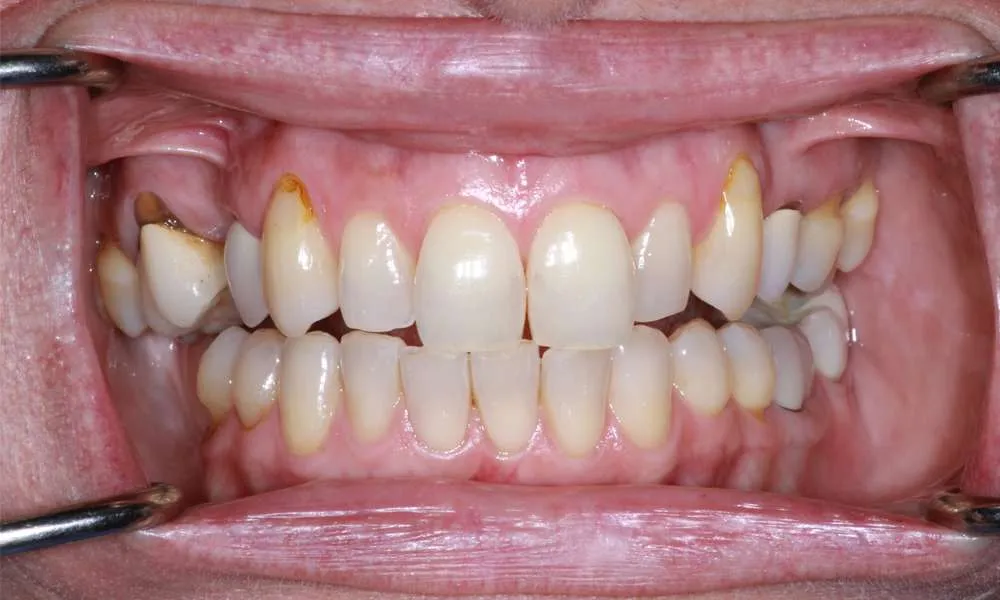

Real Stories, Real Results: Case Studies Showcasing How Our Personalized Approach Transforms Smiles and Lives

Complex Cases

Witness the Remarkable Changes We Can Achieve